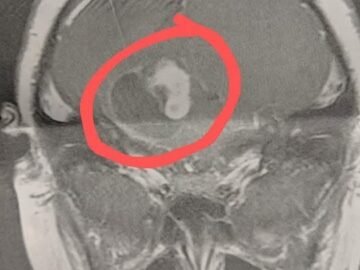

When my son was 2 1/2 years old, he was very active and a good walker. One day, he suddenly started walking like he was...